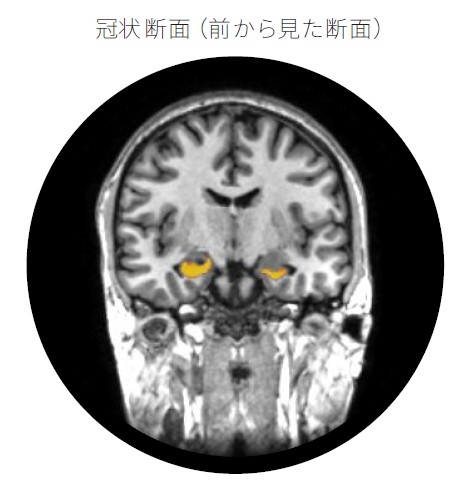

海馬はどこにあり、どのくらいの大きさですか?

海馬は大脳側頭葉の内側部にあり、タツノオトシゴのような形をしています。左右に一対ずつあり、それぞれ小指ほどの大きさです。

小指ほどの大きさしかないので、20・30代より少しずつ萎縮が進んだとしても通常のMRIと医師の目視確認だけで判別することはできませんでしたが、東北⼤学加齢医学研究所の開発したAI画像解析技術に基づき、健康なうちからの海馬の大きさを測ることができるようになりました。海馬の大きさを測ることで、脳の健康度合いを確認することができます。